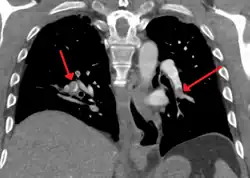

CT pulmonary angiography

CT pulmonary angiography (CTPA) is a pulmonary angiogram obtained using computed tomography (CT) with radiocontrast rather than right heart catheterization. Its advantages are that it is accurate, it is non-invasive, it is more often available, and it may identify other lung disorders in case there is no pulmonary embolism. The accuracy and non-invasive nature of CTPA also make it advantageous for people who are pregnant.[61]

On CT scan, pulmonary emboli can be classified according to the level along the arterial tree. -

Segmental and subsegmental pulmonary emboli on both sides -